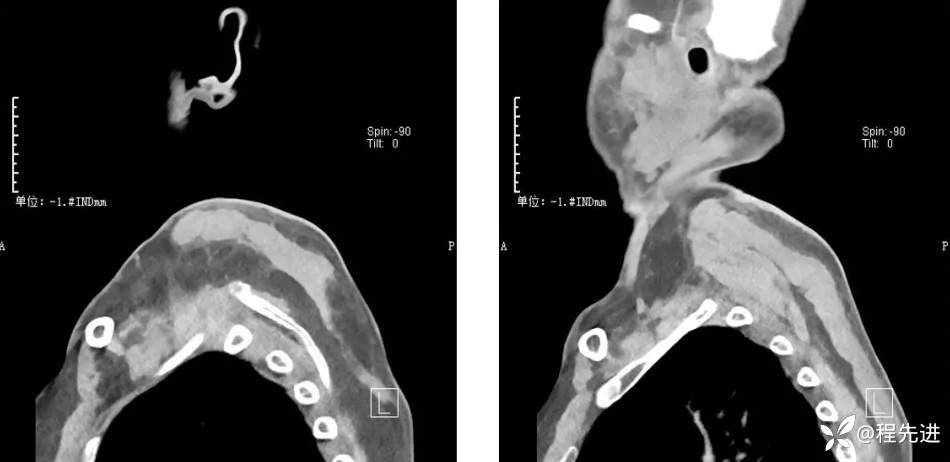

CT检查: